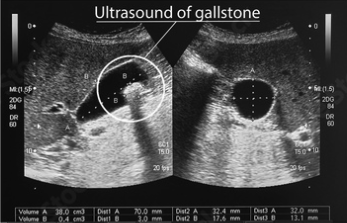

Ecografía abdominal: Es la técnica de imagen más utilizada y efectiva para detectar cálculos biliares y observar la inflamación en la vesícula.